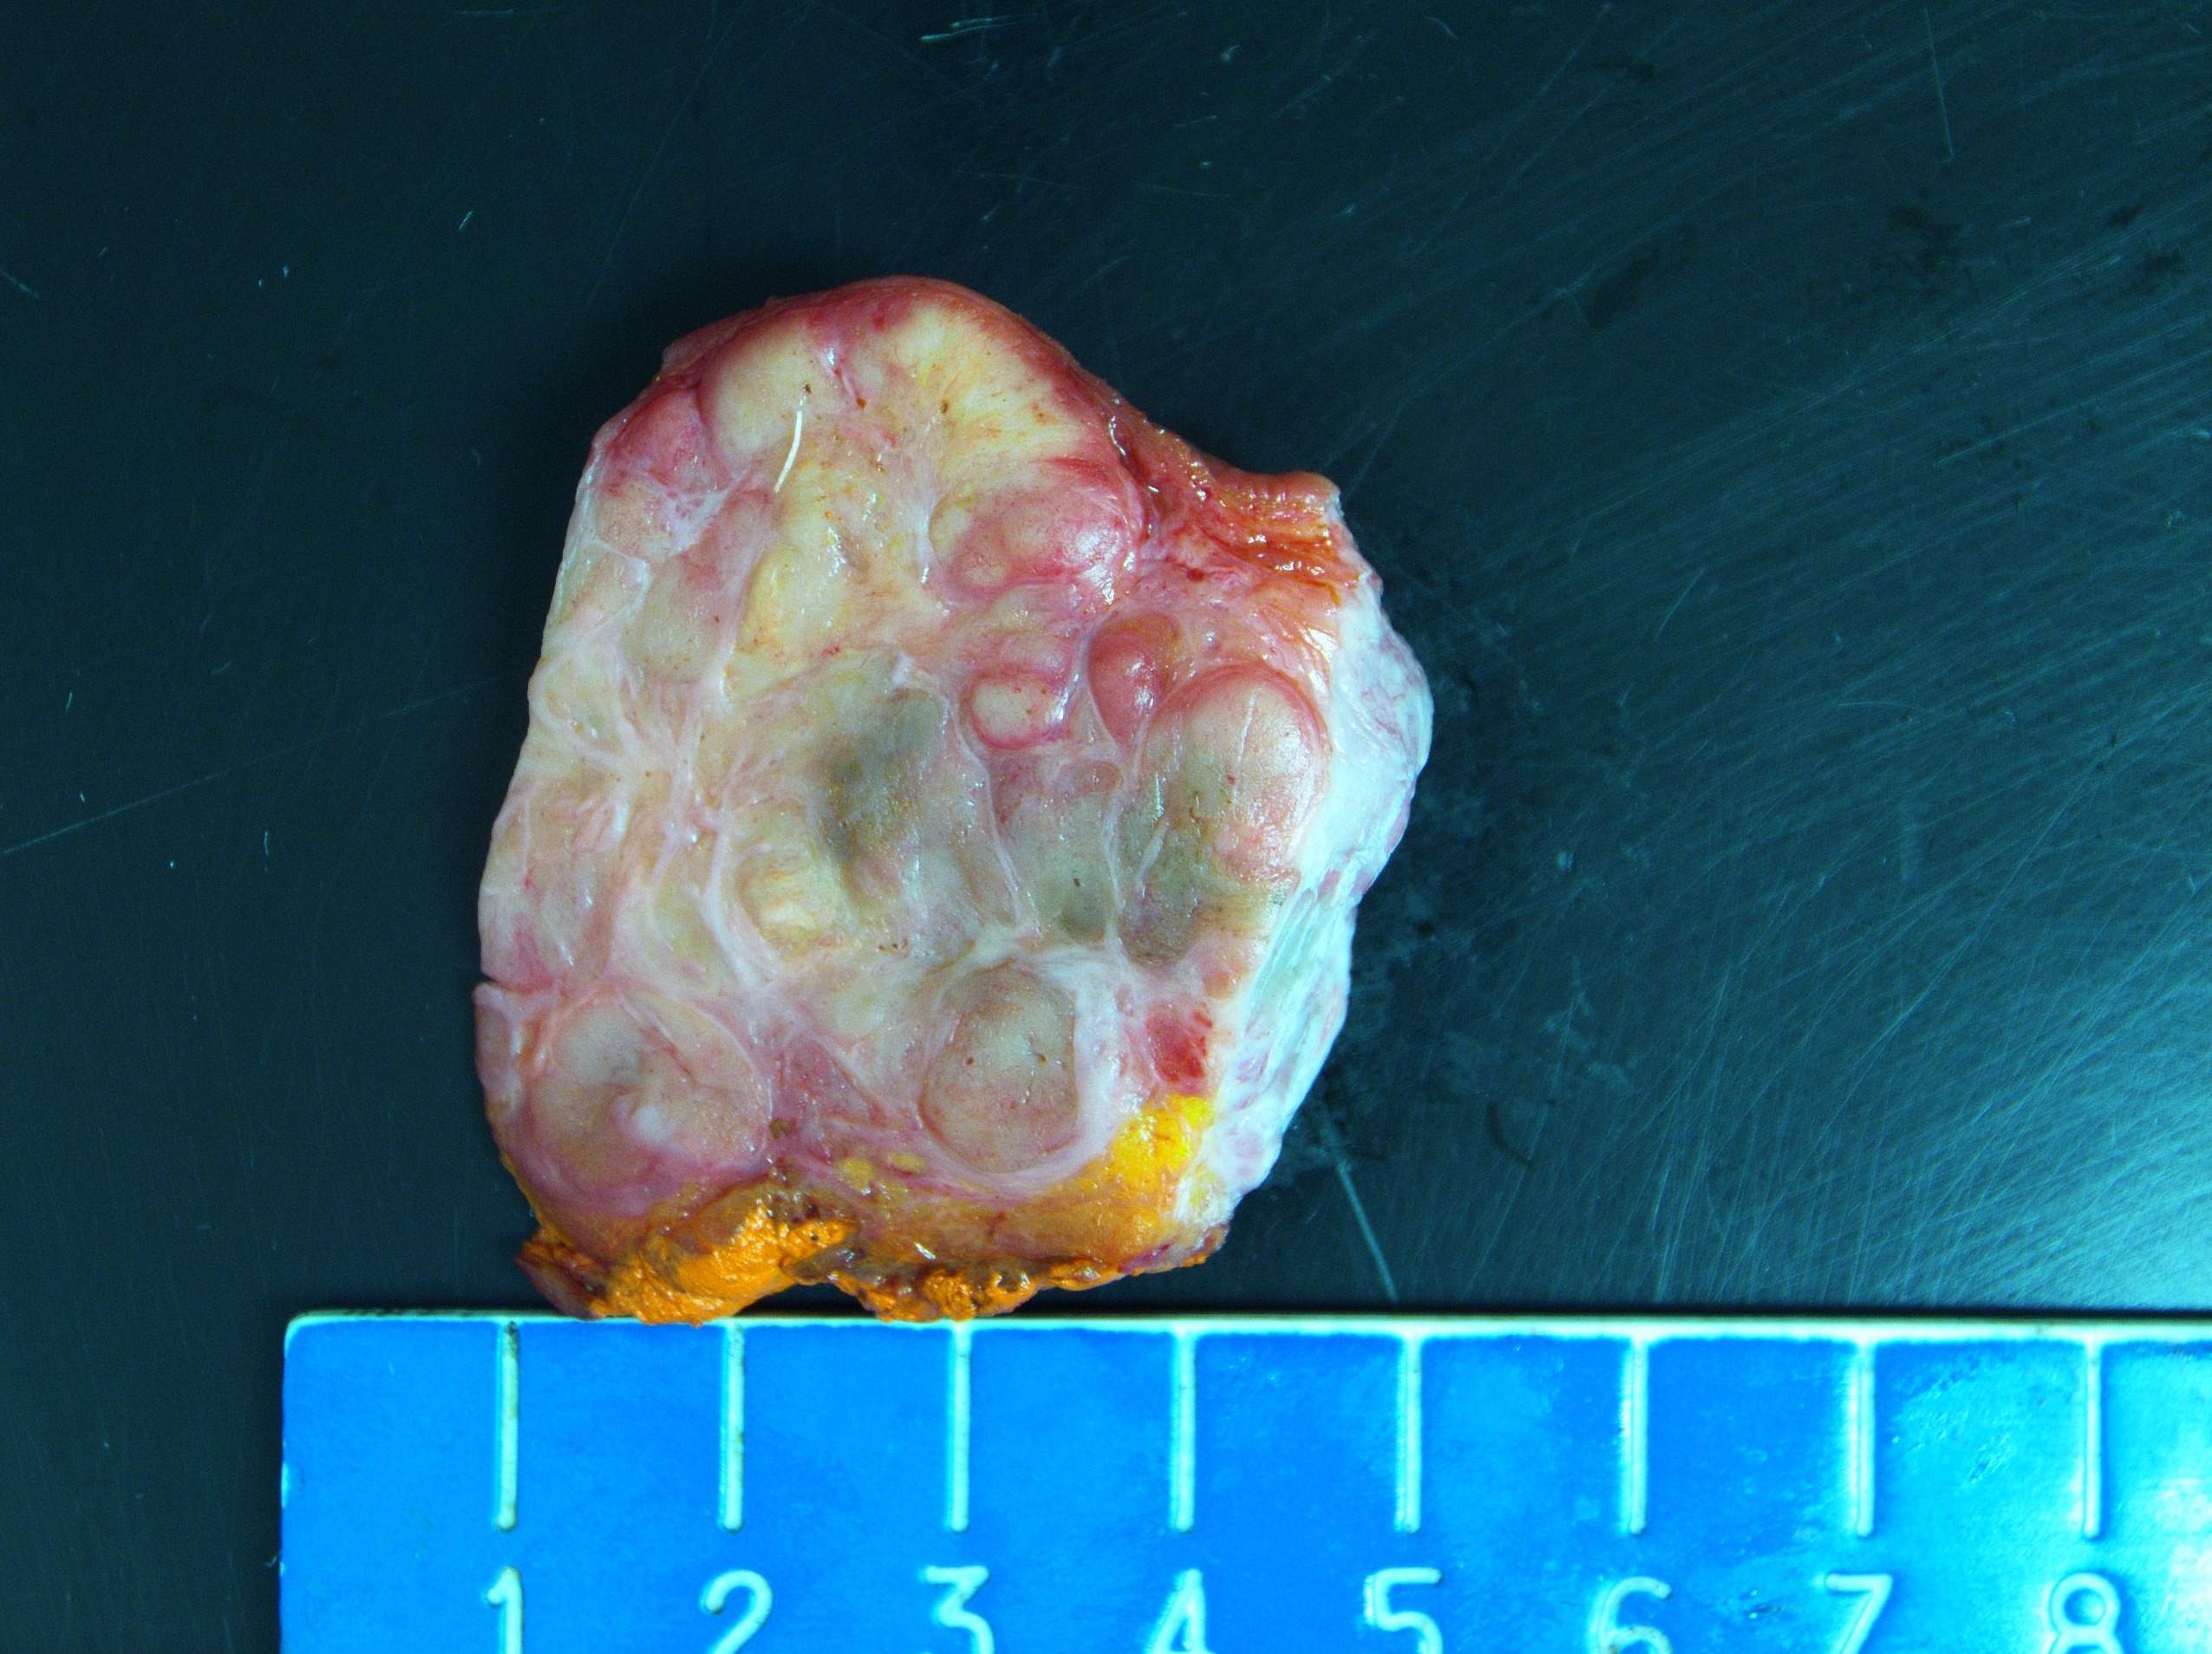

Gross description

- Genitourinary paragangliomas are typically tan-pink to violaceous, encapsulated and firm (Abdom Radiol (NY) 2022;47:1414, Abdom Radiol (NY) 2022;47:4032, BMC Urol 2023;23:21)

- Bladder paragangliomas are often submucosal or intramural and less frequently subserosal, with size at diagnosis up to 9.1 cm (mean: 3.9 cm)

- Small bladder paragangliomas: typically well circumscribed, round ovoid and homogeneous

- Larger bladder paragangliomas: usually more complex appearance with lobulation, peri and intratumoral vascularization and cystic / necrotic / hemorrhagic areas

- Bladder paragangliomas may have calcification (up to 20% of cases) or local invasion of the pelvic side wall, uterus, vagina and ovaries

Gross images